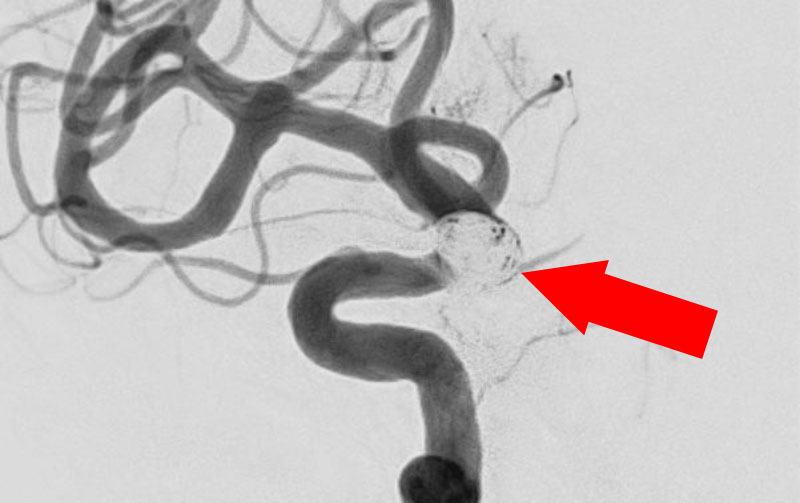

No.1630 手術前

No.1630 手術中

No.1630 手術後